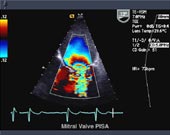

2D Echo

Two-dimensional echocardiography

can provide excellent images of the heart, Para cardiac

structures, and the great vessels. During a standard

echo, the sound waves are directed to the heart from

a small hand-held device called a transducer, which

sends and receives signals. Heart walls and valves

reflect part of the sound waves back to the transducer

to produce pictures of the heart. These images appear

in black and white and in color on a TV screen. They're

selectively recorded on videotape and special paper,

and later reviewed and interpreted by a cardiologist

(heart specialist).

From the pictures it is possible

to measure the size of each part of your heart, to

study motion and appearance of the valves and the

function of the heart muscle. Your physician uses

the measurements to determine how your heart is working

and whether or not any abnormalities are present.

A Doppler echo is often done at

the same time in order to determine how the blood

flows in your heart. The swishing sounds you hear

during the test indicate blood flowing through the

valves and chambers.